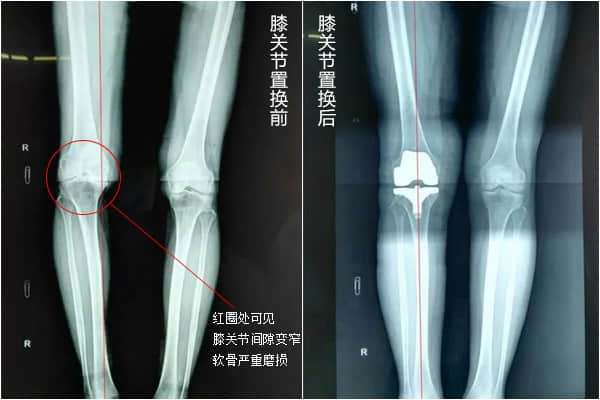

膝骨性关节炎是一种退行性病变,保守治疗无法使已经磨坏的关节软骨再长出来,而得病的患者会因疼痛和关节变形逐渐失去行动能力。这时就需要通过膝关节表面置换手术来彻底解决问题。

膝关节置换手术的优点:术后可以解决关节疼痛的问题,让关节屈曲度更好,让病人重新能够站立和行走,恢复生活自理能力,甚至重新回到工作岗位;术后膝盖畸形得到矫正,双腿更直,让患者重拾自信。